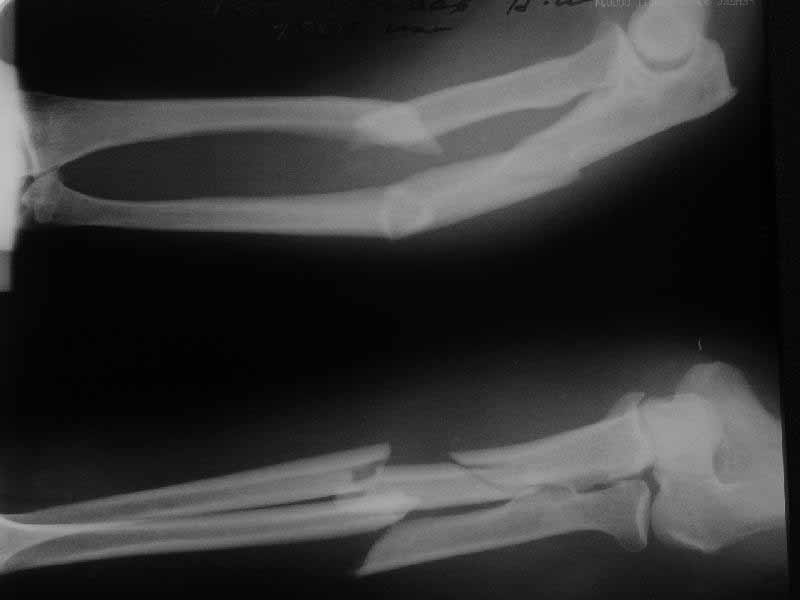

He just visited the clinic in 3 months after the surgery. X-rays

attached. He ignored any physio and ROM excersices so his

functional status is not the best i ever seen.